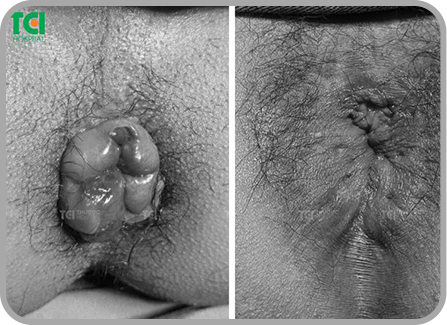

Các tình trạng sau xảy ra trong thời gian dài: Chảy máu khi đại tiện thường xuyên, ngứa ngáy, cộm, rát ở hậu môn, thấy vướng víu và có búi sa ra hoặc búi trĩ nằm mọc ở ngay rìa hậu môn đau đớn nghiêm trọng, khiến người mắc ngồi, nằm hay đi lại đều khó khăn và bất tiện.. là những dấu hiệu rất rõ ràng cho thấy bệnh trĩ.

Bệnh trĩ là tình trạng là bệnh lý hậu môn trực tràng phổ biến, xảy ra khi các tĩnh mạch ở hậu môn và trực tràng dưới bị giãn và phình to, tạo thành các búi trĩ. Có 3 loại trĩ: Trĩ nội (Trong hậu môn, trên đường lược, sau đó sa ra ngoài, chia độ I,II,III, IV theo mức độ sa); Trĩ ngoại (ngoài hậu môn, dưới đường lược, không phân độ và được phân biệt theo trĩ ngoại nhẹ - trĩ ngoại nặng); Trĩ hỗn hợp (kết hợp trĩ nội và ngoại).